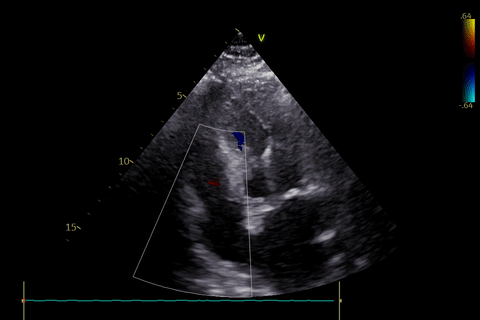

术前超声评估:

主动脉瓣狭窄(重度),收缩期主动脉瓣上流速增快,最大流速约4.5m/s,最大压差约82mmHg,平均流速约3.3m/s,平均压差约49mmHg。左室肥厚,左室舒张功能减低。D-Dimer5.22mg/1FEU,NT-proBNP780.3pg/ml,hsTNI最高270pg/ml,CK-MB最高4.9ng/ml,肌酐56μmol/L,血钾3.7mmol/L。双下肢大动脉超声显示双侧股动脉多发斑块。双侧锁骨下动脉超声未见明显异常。双侧颈动脉超声显示颈动脉内中膜增厚、斑块形成。双下肢深静脉超声显示双下肢深静脉未见血栓。主动脉+腹主动脉+髂动脉CTA:主动脉、髂动脉粥样硬化,主动脉瓣钙化。冠脉造影显示RCA中重度狭窄,于RCA植入支架2枚。